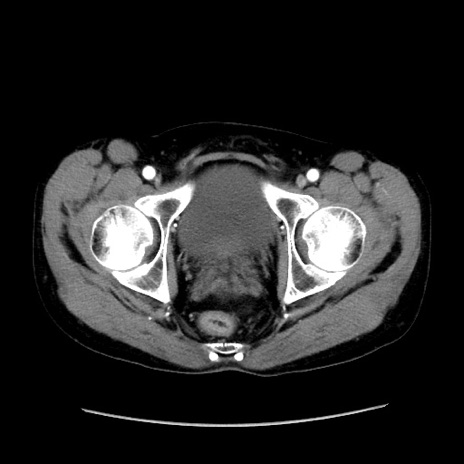

症例37(横断像)

【症例】40歳代 男性

【主訴】腹痛

【現病歴】4時間ほど前に電車に乗車中に臍部上より腹痛出現。徐々に増悪し起立困難となり、救急外来受診。生ものは数日食べていない。今朝お雑煮を食べた。

【身体所見】BT 36.8℃、BP 117/84mmHg、HR 91/min、SpO2 97%、苦悶様、腹部:臍上部広範囲圧痛あり、反跳痛±

【データ】WBC 8100、CRP 0.03